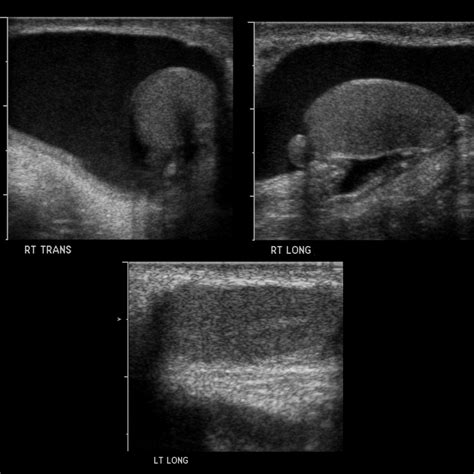

• Ultrasound (Sonography): Preferred for its ability to produce high-quality images without any radiation, making it ideal for abdominal or soft-tissue issues.

Ultrasound None Abdominal organs, neonatal brain, appendicitis